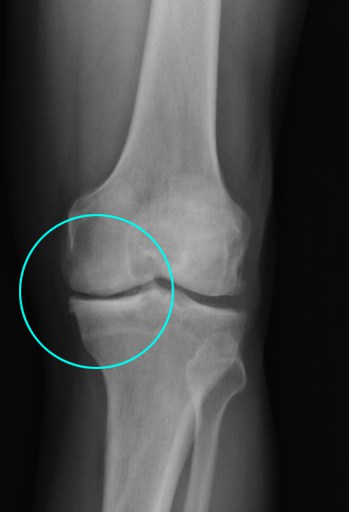

Artrosis de Rodilla: ¿Qué es? Síntomas, Diagnóstico y Tratamientos   ¿Qué es la Artrosis de Rodilla? La articulación de la rodilla está formada por el fémur, en la parte superior, y por otra, la tibia y el peroné. Estas superficies están tapizadas por el cartílago articular. La artrosis de rodilla se caracteriza por el deterioro

La artrosis es la enfermedad degenerativa articular más frecuente, caracterizada por la destrucción del cartílago que recubre los huesos y que hace de amortiguador, favoreciendo el movimiento. Se trata de una enfermedad que sufre entre el 5% y 15% de la población en Argentina. Células Madre en Artrosis de Rodrilla La rodilla es una de